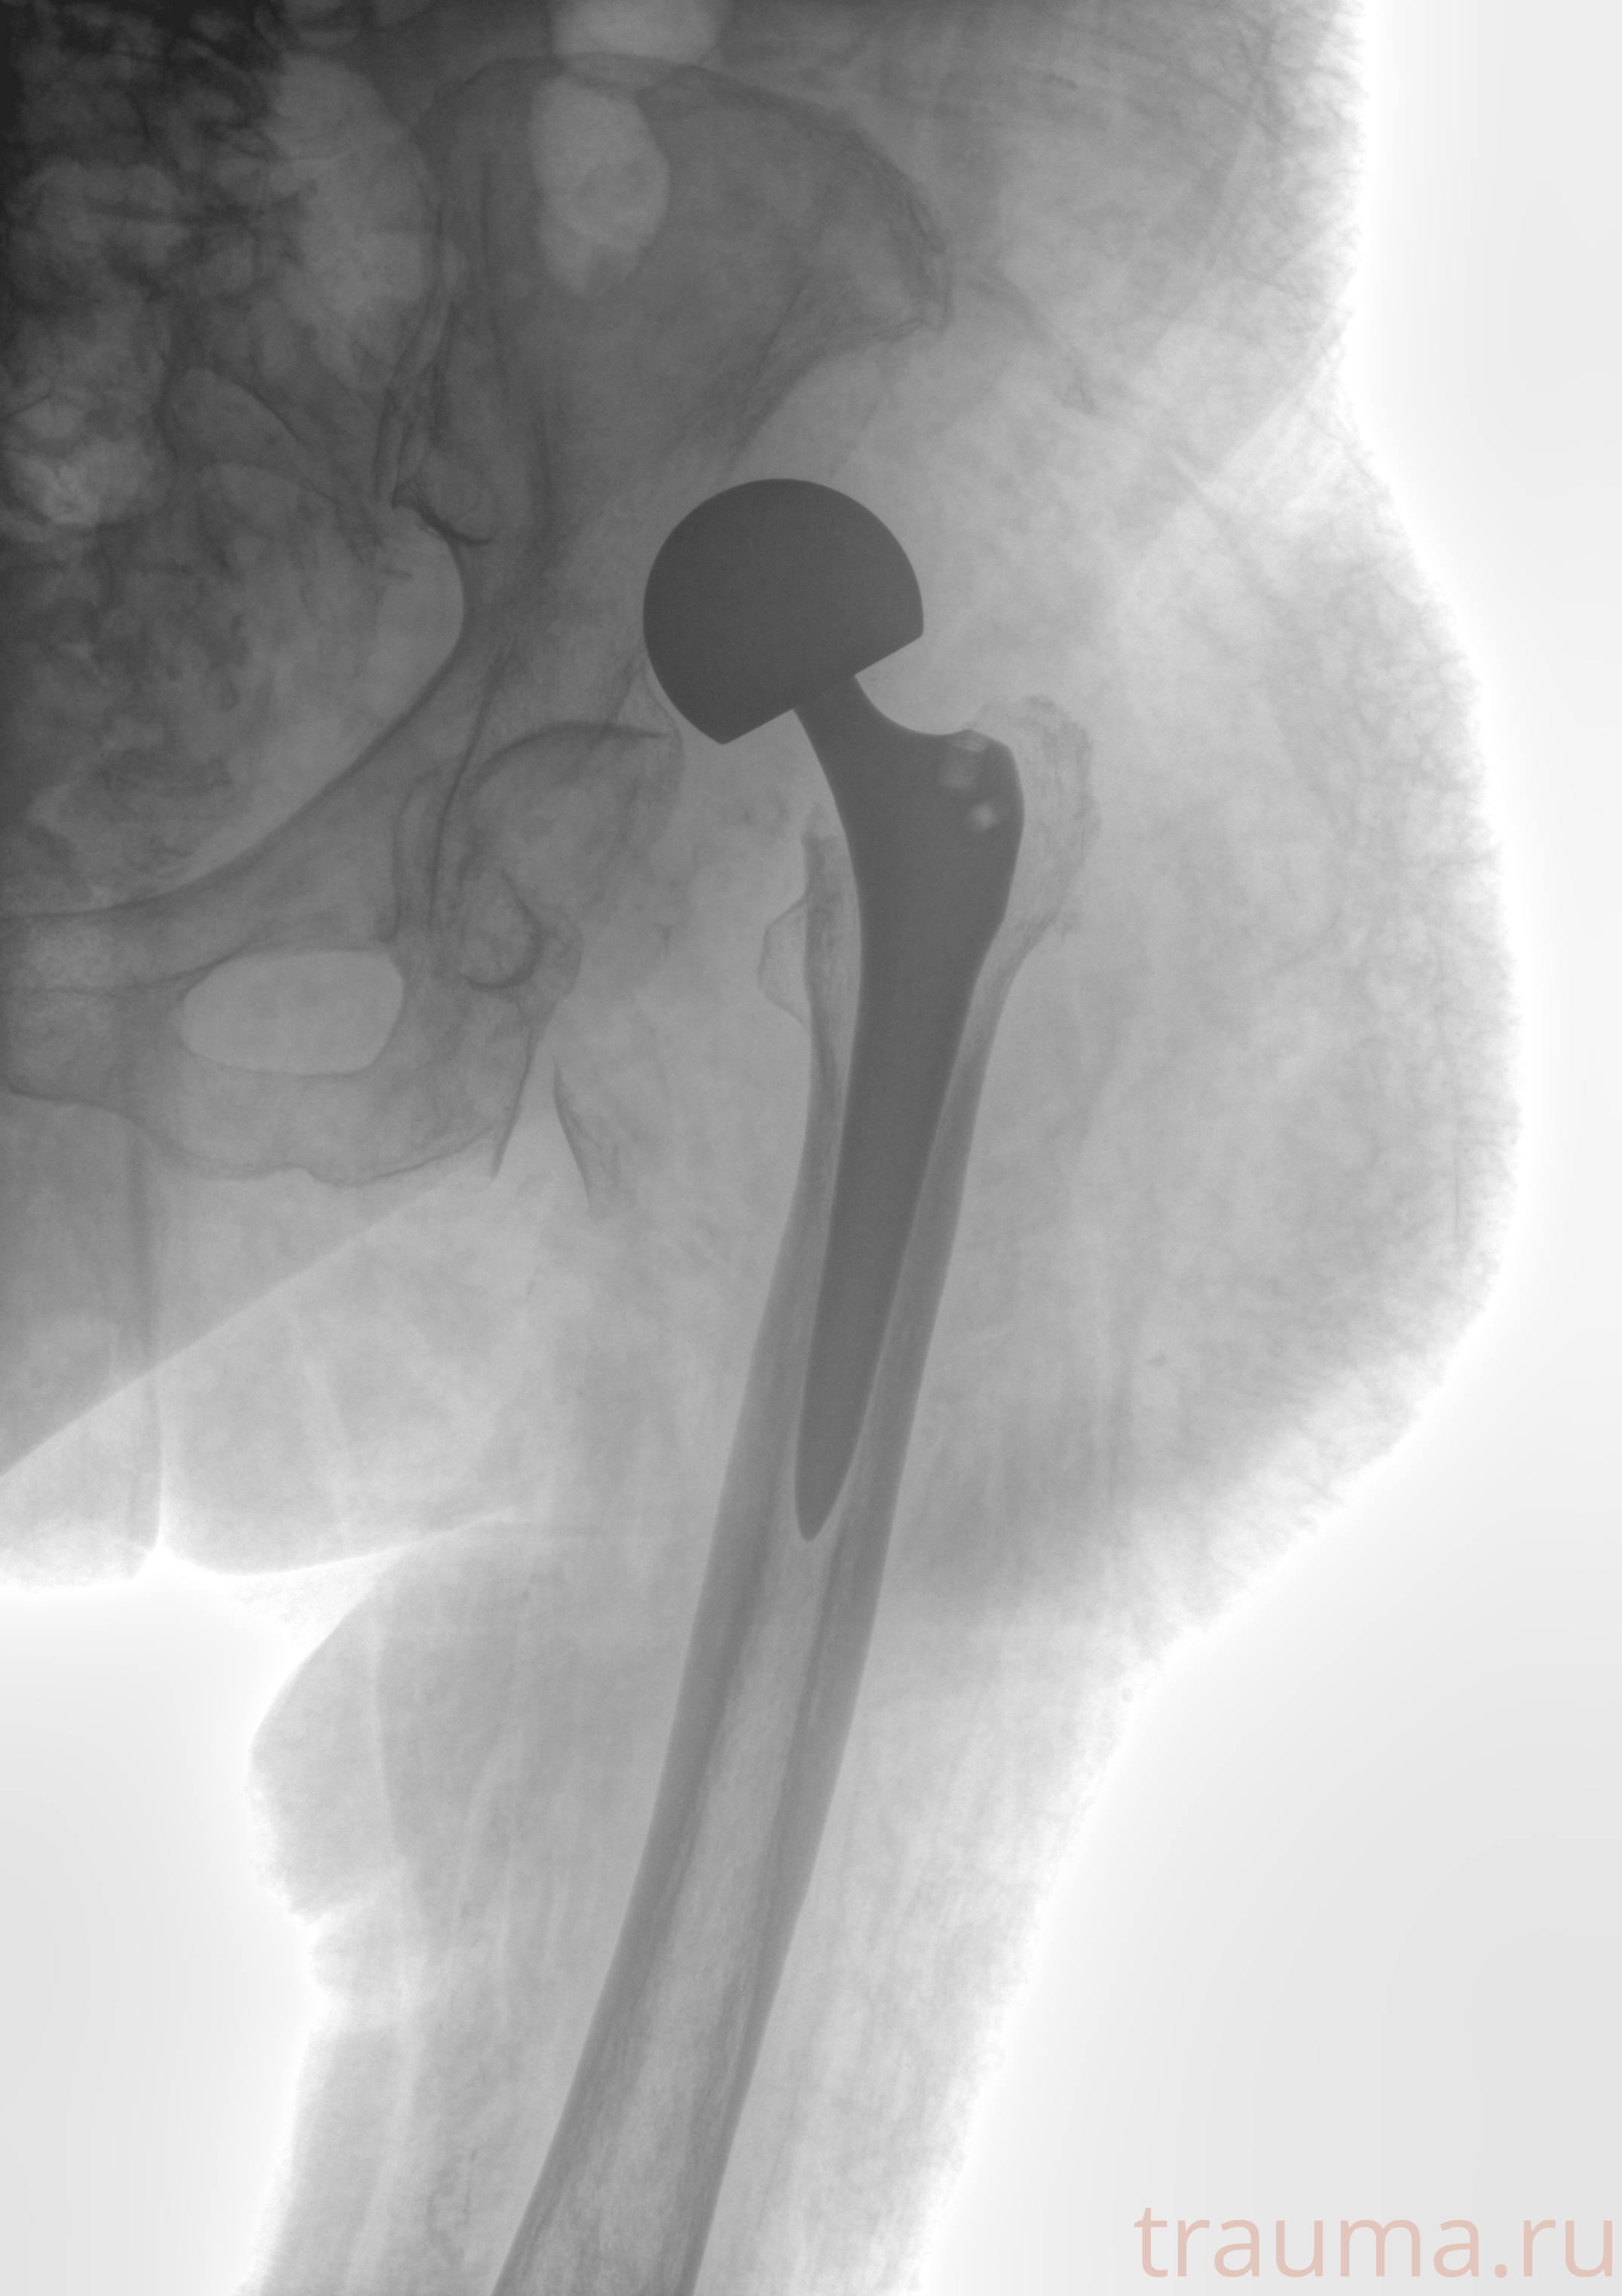

Рентген на дому: по вашему адресу приезжает врач-рентгенолог, травматолог-ортопед с мобильным рентгеновским аппаратом, проводит диагностику травмы или заболевания, делает необходимые рентгенограммы, дает рекомендации по дальнейшему лечению. Получить качественные снимки в домашних условиях возможно благодаря уникальной методике, разработанной МосРентген Центром для института  Склифосовского